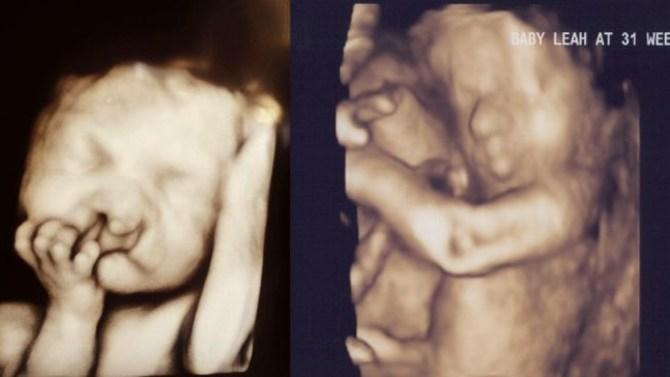

Medicii Au Sfătuit O Să Facă Avort Cand Au Văzut Ecografia 4d